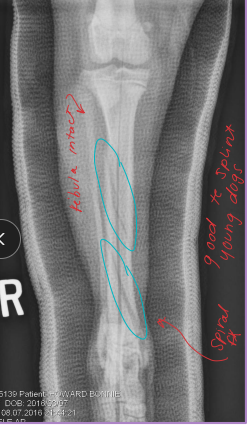

Common in young animals (open physes)

Pattern: Transverse, Oblique, Spiral, Comminuted

Young animals, open growth plates

Exception is physeal fractures in young dogs (can be sole implant)

Why: physeal fractures

femur, tibia

What: Small smooth IM pins

How: inserted laterally, cross physis and eachother